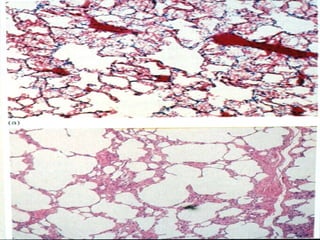

Gas exchange occurs in the  alveoli

Alveolar macrophages  (dust cells) are migratory cells that constantly crawl within the alveoli, engulfing microbes and foreign material that has reached the alveoli.

The terminal bronchi empty into the thin-walled  alveoli